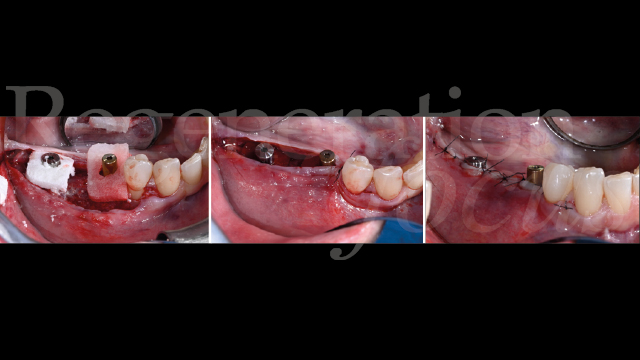

L’intervento chirurgico è stato eseguito in anestesia loco-regionale. È stato elevato un lembo trapezoidale composto da un’incisione crestale e da un’incisione verticale di svincolo posizionata due elementi mesialmente al difetto, mentre distalmente l’incisione è proseguita nella regione retromolare (Fig. 4). Particolare attenzione è stata posta al rilascio periostale, eseguito sia vestibolarmente che lingualmente, permettendo una mobilizzazione coronale di entrambi i lembi di circa 8 mm senza tensione.

La mesh customizzata si è adattata perfettamente al sito ricevente, confermando la precisione della pianificazione digitale (Fig. 5). Il materiale da innesto è stato preparato combinando osso autologo particolato, raccolto dalla linea obliqua esterna mediante grattino monouso (SafeScraper, Meta), con osso bovino deproteinizzato di granulometria 0,25-1 mm (Geistlich Bio-Oss®) in rapporto 50:50. A questa miscela sono stati aggiunti 0.3 ml di gel a base di polinucleotidi e acido ialuronico (Regenfast®), creando una mixture bioregenerativa che è stata accuratamente compattata all’interno della mesh (Fig. 6).

La fissazione è stata ottenuta mediante tre viti in titanio da 1.5×5 mm (Viti FYxoss, MCbio) posizionate strategicamente (Fig. 7). Una membrana in collagene 30×40 mm (Geistlich Bio-Gide®) è stata posizionata a copertura della mesh (Fig. 8). La chiusura primaria tension-free è stata ottenuta con suture orizzontali a materassaio e punti staccati (Fig. 9).